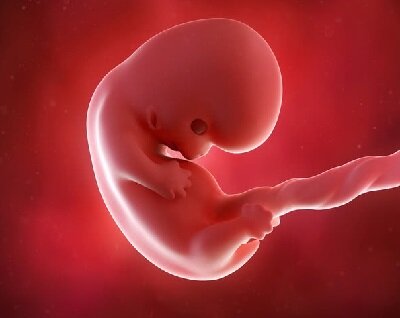

На 8 недели беременность зародыш приобретает статус эмбриона.

Сейчас у малыша образовывается верхняя губа и формируется контур носика, выделяются его крылья и кончик (правда он еще не функционирует и полностью покрыт слизью), зачатки век и ушные раковины (продолжает развиваться внутреннее ухо, сложная система, которая будет развиваться еще несколько лет после рождения). Начали функционировать почки, а в желудке вырабатывается желудочный сок. Подходит к концу формирование сердца. Зачатки всех жизненно важных органов уже заложены и начинают стремительно развиваться.

На крохотных ручках и ножках уже заметны маленькие пальчики, суставы становятся более подвижными, эмбрион начинает сгибать и разгибать конечности.

На языке образуются вкусовые сосочки.

Почки начали выделять мочу.

Маленькое сердечко уже стало четырехкамерным и во всю перекачивает кровь.

Продолжает развиваться нервная система, малыш начинает активно двигаться, это заметно по УЗИ. Но почувствовать шевеления вряд ли удастся, эмбрион еще слишком мал.